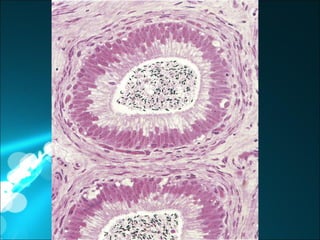

Cada testículo está rodeado por una cápsula de tejido conectivo  denso irregular, colagenoso, llamado túnica albugínea. Mas profundo a esta se encuentra capa de tejido conectivo laxo  muy vascularizado, llamado túnica vascular. Hacia posterior de la túnica albugínea, esta engruesa, formando así el mediastino testicular

Cada testículo estárodeado por una cápsula de tejido conectivo denso irregular, colagenoso, llamado túnica albugínea. Mas profundo a esta se encuentra capa de tejido conectivo laxo muy vascularizado, llamado túnica vascular. Hacia posterior de la túnica albugínea, esta engruesa, formando así el mediastino testicular